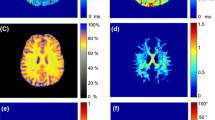

a \(b=0\) s/mm\(^2\) image for the default (0\(^{\circ }\)) and tilted (18\(^{\circ }\)) orientation registered to the halfway-tilted (9\(^{\circ }\)) space, and their difference (tilted—default). \(\hat{\sigma }\) is the estimated standard deviation in the background of the image. b Estimated \(T_2\) for the default (\(0^{\circ }\)) and tilted (\(18^{\circ }\)) orientation registered to the halfway-tilted (\(9^{\circ }\)) space, and their difference. Red arrows indicate regions of visible difference

Voxel-wise \(T_2\)-estimates. Figure 5b highlights differences in estimated \(T_2\) for different coil-orientations. Globally, the difference in \(T_2\)-values estimated from the data in default and tilted head orientations is larger than or equal to \(T_2\)-values estimated from test-retest scans in default head orientation for subject 1 (Fig. 5b, left half). Local differences in \(T_2\) can be observed between the default and tilted position, as indicated by red arrows in the \(T_2\)-maps in Fig. 5b, for example. The inverse \(T_2\)-values in white matter mostly range between 9 s\(^{-1}\) and 21 s\(^{-1}\) for both subjects and head orientation.